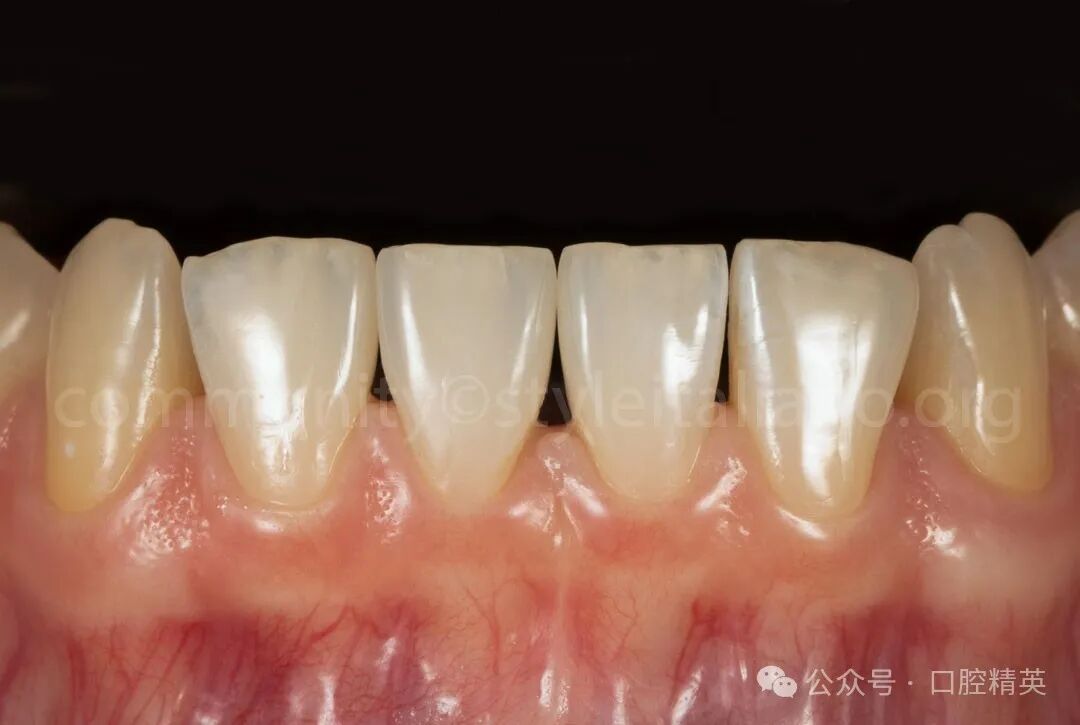

图7 粘接完成后,调颌、抛光。

图8 抛光也是在橡皮障隔离下进行的,这有助于最大限度地降低牙龈损伤的风险,并提供了更有效和可控的工作流程。